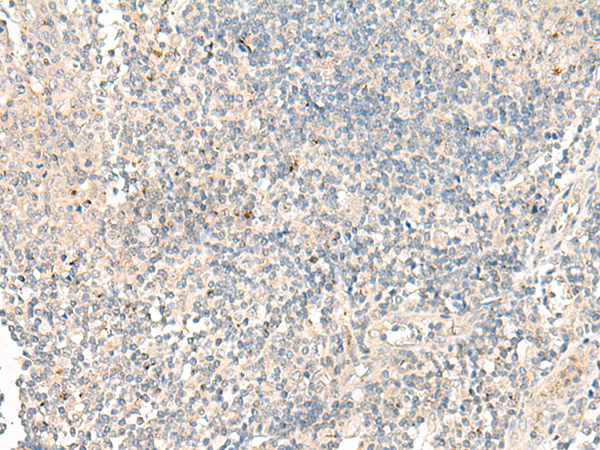

分类: 科研抗体货号: P06608别名: RP78; P114-RhoGEF应用: IHC反应种属: Human